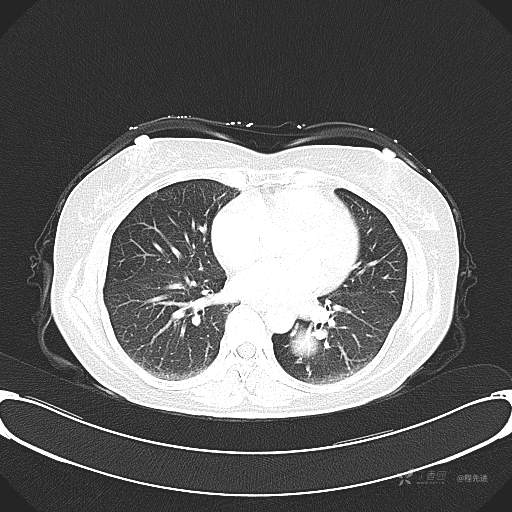

患者性别:女

患者年龄:57岁

简要病史:体检发现

CT增强

平扫CT值约40HU(未上传图像),增强后动脉期CT值约70HU,静脉期CT值约97HU。